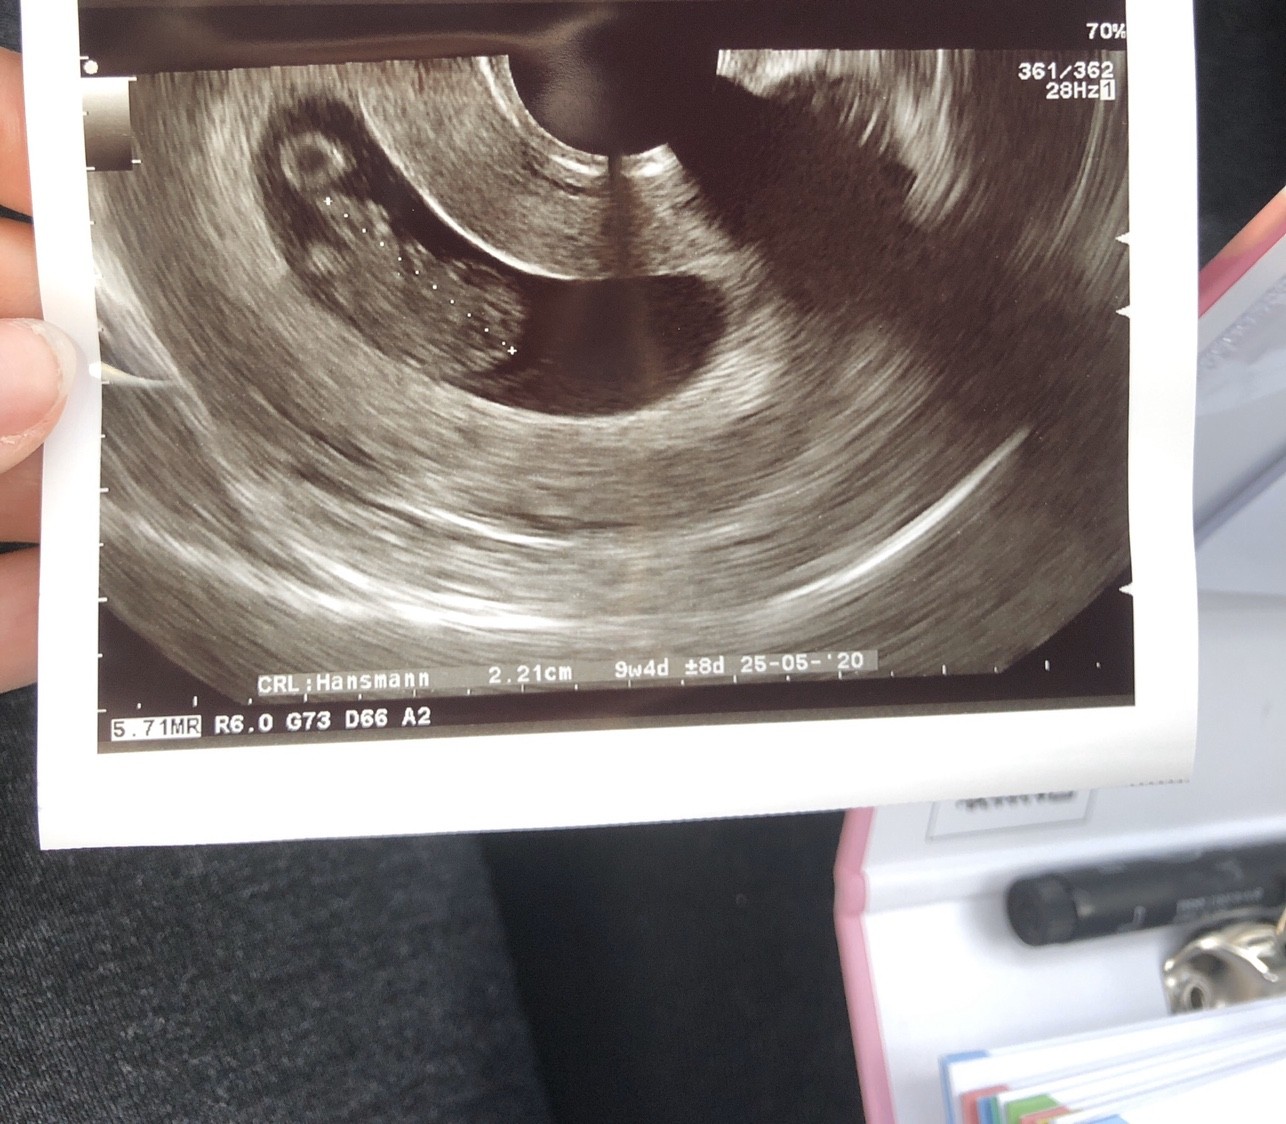

Boże a ja dziś zaczęłam plamić, brzuch boli, plecy bolą, długo nie myśląc wzięłam syna pod pachę i do swojego lekarza. Nie zauważył nic niepokojącego. Możliwe ze po stosunku i mamy się wstrzymać... zwiększył mi duphaston i nadal plamie :/ ale z dzidza ok, rośnie, dziś już wyglądała tak

Zobacz załącznik 1038049

9+4 - no to prawda martwią ;/ szczególnie ze pierwszy raz mam coś takiego :( oby szybko zniknęły